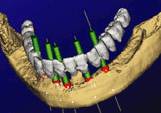

Materialise (Belçika) firması, SimPlant yazılımı yardımıyla implant uygulama tasarımı yapmaktadır. İmplant cerrahisinin planlanmasında kemik densitesi, kompakt/spongiöz kemik oranı ve anatomik oluşumlar açısından 3 boyutlu olarak çene kemiği analizi önem taşımaktadır. Tüm radyografik tetkik tekniklerinin avantajlarını bir arada bulunduran SimPlant yazılımı sayesinde kişiye özel hassas implant cerrahisi planlaması yapılabilmektedir.

Yapılan planlamaya göre hassas ve hatasız bir şekilde cerrahinin gerçekleştirilebilmesi için hastaya ait özel delme kılavuzlarının 3D olarak tasarlanmasını sağlamaktadır. Daha sonra bu klavuzlar SLA cihazları yardımıyla üretilmektedir. Bu klavuz apareyler sayesinde frez giriş yolu gibi implant cerrahisinin başarısını etkileyen birçok parametre, 3 boyutlu olarak önceden saptanmış olur. Dolayısı ile implant cerrahisi sırasındaki birçok olası komplikasyon bu şekilde önlenebilmektedir.

1- 3D Görüntüleme ve implant yerleştirme planlaması

2- Hastaya Özel delme klavuzu SLA ile imal edilmiş ve damak modeli üzerine oturtulmuş

3- Kesit: Çene kemiğine klavuz ile delme. Kırmızı renkle gösterilen parça, hastaya özel yapılmış olan delme klavuzudur.